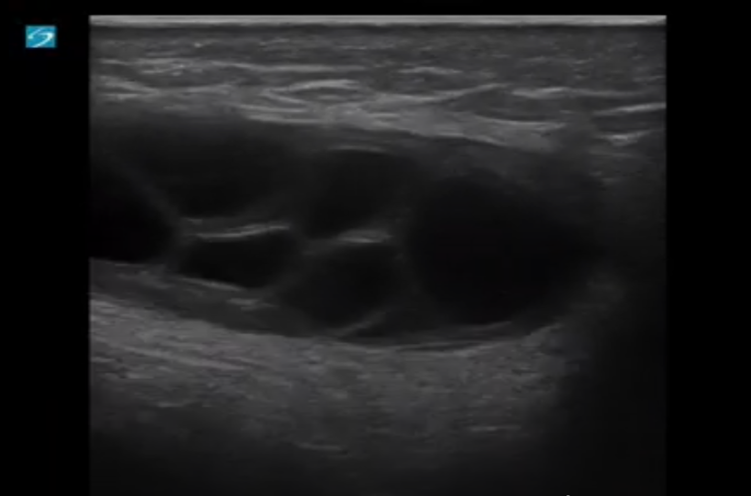

Bedside ultrasound was performed and demonstrated an oval-shaped, heterogeneous mass in the right inguinal region. The differential diagnosis included a bowel- or fat-containing hernia, hernia with ovarian content, enlarged lymph node, malignancy, or vascular malformation. The mass was located superficial to the abdominal musculature. The bladder and pubic bone were visualized. Further ultrasound examination revealed a hernia sac extending toward the labia, containing a heterogeneous mass with multiple embedded anechoic cystic structures. Color and pulse wave Doppler demonstrated internal vascular flow.

Image 1: Mass found on ultrasound